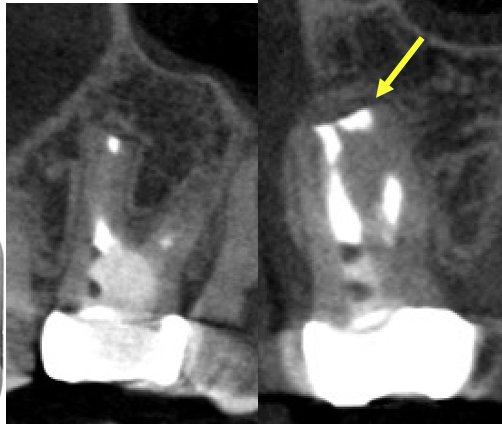

術前、右上2に大きな透過像(黄色矢印、炎症の黒い影)と左上1にも透過像(赤矢印)が見られます。腫れの原因は、歯髄壊死と根尖性歯周炎と診断し、まずは根管治療を行いました。左上1の根尖も透過像(緑矢印)がありましたが、歯髄の反応は正常でしたので歯髄壊死とは診断せず治療は行いません。

• 根管治療後4ヶ月、左上1の透過像(赤矢印、黒い影)は小さくなり治癒傾向が確認できますが、右上2(赤矢印)は以前より広がってきていて、腫脹の再発がありました。非治癒判定となり、次の治療法として歯根端切除術を行うこととなりました。歯根端切除術を行わない医院ではこの時点で抜歯が宣告されてしまうでしょう。